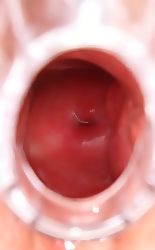

WEBCAMS